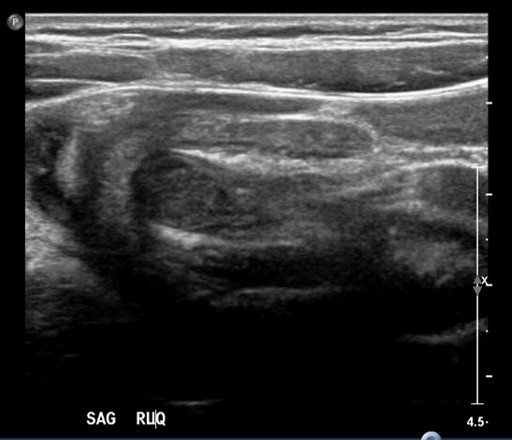

Significant findings:

The patient’s abdominal ultrasound revealed intussusception in the right upper abdominal quadrant. The transverse ultrasound view showed a “doughnut sign” (dashed yellow line), telescoping bowel (yellow arrow), and invaginated hyperechoic mesenteric fat with crescent configuration (dashed orange line). The sagittal ultrasound view demonstrated the intussusception formed by the outer recipient bowel loop (yellow arrows), invaginated hyperechoic mesenteric fat (orange asterisks), and telescoping bowel centrally (red arrow).